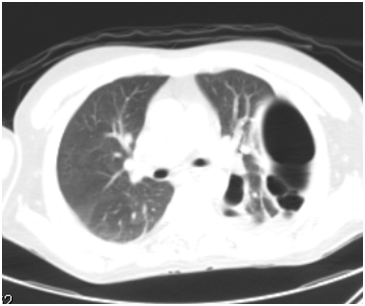

After five days patient returned with the complaints of persistent headache, nasal obstruction, rhinorrhea, right-sided otorrhea and dry cough. He was sick and but still afebrile. He was admitted and right ear swab was sent for culture and sensitivity. The nasal and ear swabs yielded no growth. He was put on IV antibiotics with nasal and antral irrigations twice-daily. His baseline blood works including CBC and renal functions were normal but ESR was 88mm. c-ANCA was sent as Wegener’s granulomatosis was also one of our differential diagnoses. Chest x-ray was within normal except for a left hilar shadow (Figure 1). Biopsy taken under local anesthesia from the edges of septal perforation was reported as non-specific inflammation.

Figure 1 Left hilar opacity.